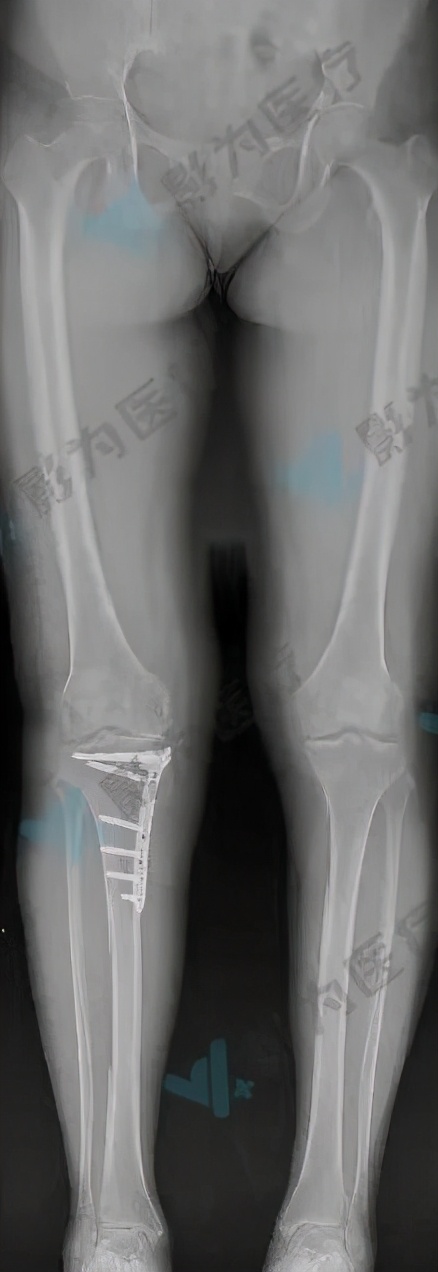

术后评估

术前规划胫骨近端内侧角95°,术后X光分析胫骨近端内侧角94.11°,误差0.89°,达到了预期的效果。患者术后恢复良好,目前已康复出院。

术后X光片